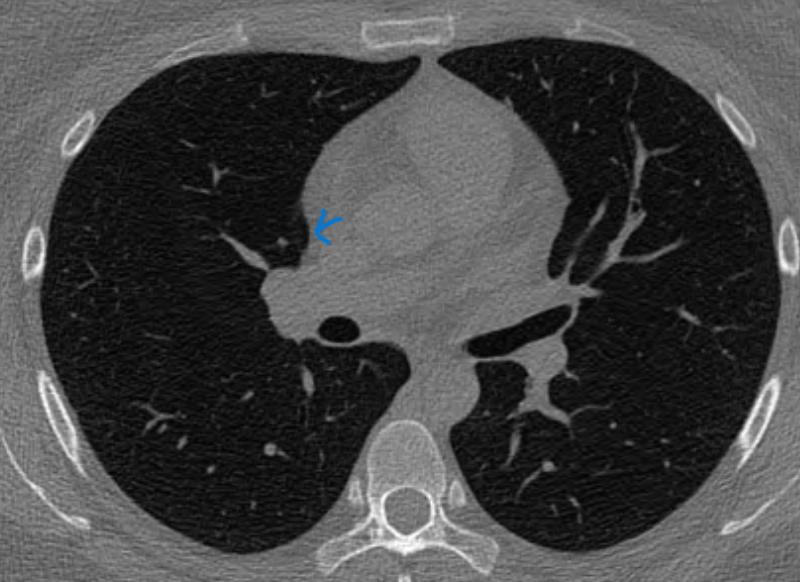

폐결절 고형으로도 보이고 간유리로도 보이면 무엇인가요?

일단은 판독전 간유리라고 들었는데

1슬라이드이선 하얀색 2슬라이드에선 음영진튼 회색 3슬라이드에선 아주연한 회색등..이면

순수가 아닌 고형있는 간유리일 확률이 있는건가요?

사진 봐주시길 부탁두려요

3thk 적혀있는거 제외하고 1thk입니다

밝고 선명한건 AI가 발견한것으로 두번째 사진이랑 같은거 같습니다.

CT를 확인하시고 간유리음영이라고 들었는데 영상을 직접 확인하시고나니 조금씩 차이가 나서 헷갈리시는 것 같습니다.

일단은 첫번째 영상은 크기가 애매해서 말씀드리기는 어려운 것 같구요

둘째 영상과 셋째 영상은 둘다 간유리음영으로 보셔도 될 것 같습니다.

물론 둘째 영상보다 셋째 영상이 더욱 흐지부지하게 보이기는 하지만

그렇다고 둘째 영상이 고형성이라고 보기는 어려울 것 같습니다.

따라서 현 영상만으로 보다면 간유리음영이라고 생각을 하셔도 될 것 같으며

일부 고형성 결절 부분을 포함하고 있다는 걱정은 굳이 하지 않으셔도 될 것 같습니다.

물론 이후 정식 판독 소견이 나오면 꼭 확인을 해보시면 되겠습니다.